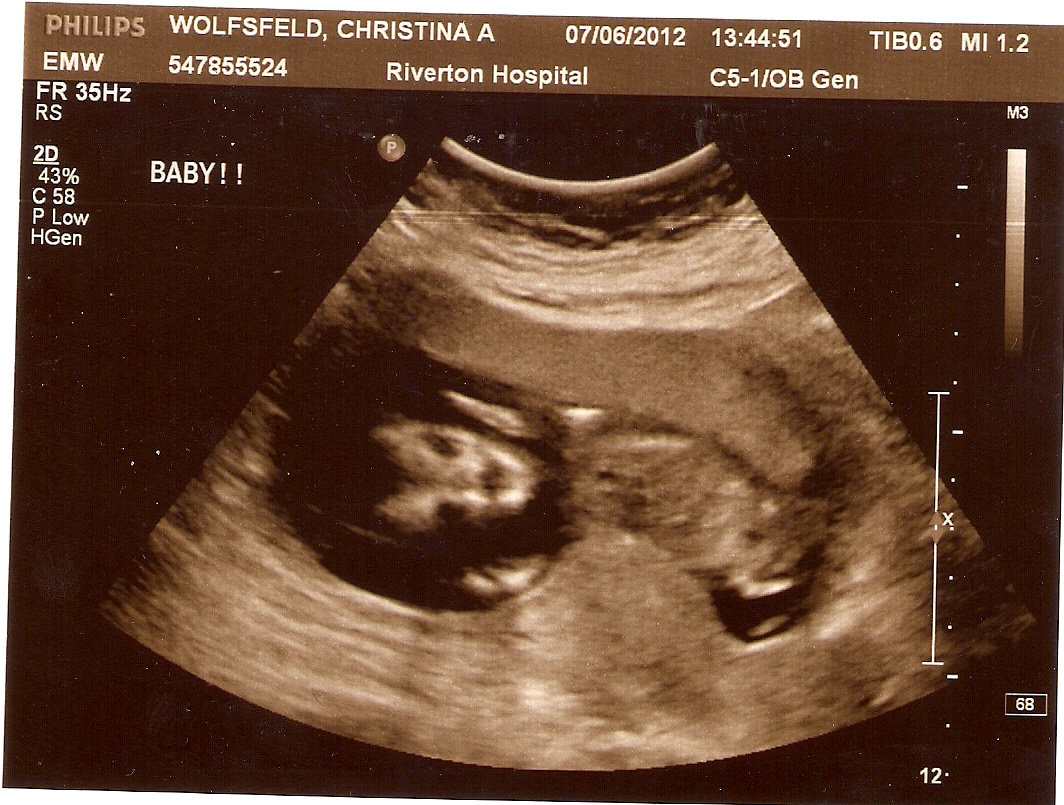

Скорее всего, вы уже посетили женскую консультацию или гинеколога, встали на учет и выполнили все полагающиеся на данном сроке исследования. Если нет, у вас есть еще несколько дней для проведения первого скрининга. Он состоит из УЗИ (на котором вы можете попросить распечатать фото вашего животика) и биохимического анализа крови на ХГЧ и РАРР-А (о чем подробно мы рассказывали в предыдущей статье).

Размер плодного яйца на 11 неделе беременности на фото УЗИ равен в среднем 65 мм, при этом длина от темени до копчика может достигать 80 мм. С этой недели специалисты УЗИ особое внимание обращают на БРП – расстояние между теменными костями, которое говорит о развитии мозга малыша. В норме бипариетальный размер сейчас составляет 24 мм, повышенные цифры могут свидетельствовать о наличии патологии.

Важно! Если будущая мама к 11-й неделе еще не стала на учёт, как раз самое время сделать это. На этом сроке проводится первое плановое УЗИ, которое помогает определить точный срок беременности, уточнить количество плодов и выявить возможные отклонения в развитии малыша.

11 недель являются знаменательным сроком, поскольку именно в этот период проводится важное обследование — первый пренатальный скрининг, направленный на выявление возможных пороков плода (в частности, синдрома Дауна – наличие дополнительной 21-й хромосомы). Он представляет собой комбинацию ультразвукового и биохимического (анализ крови) исследования. Помимо выявления возможных пороков плода, первый плановый ультразвуковой скрининг отвечает на многие другие вопросы – о сроке беременности, росте и развитии малыша, состоянии хориона, будущей плаценты и т.

Одиннадцатая неделя беременности — это время тройного теста, необходимого для полной оценки развития плода. Проще говоря, именно в это время врач назначает важные процедуры, которые помогают определить риск отклонений у крохи.

Не менее важно на данном этапе пройти УЗИ. Исследование поможет врачу узнать все детали: каков объем околоплодных вод, как развиваются конечности ребенка и многое другое.

На этой неделе пренатальный генетический скрининг может быть продолжен тестом на затылочную прозрачность. Скрининг затылочной прозрачности — это ультразвуковое исследование, которое измеряет заполненное жидкостью пространство за шеей ребенка.

Однако это всего лишь отборочный тест. Результаты, выходящие за пределы допустимого диапазона, не означают, что у вашего ребенка хромосомные проблемы, но они означают, что ваш врач, скорее всего, порекомендует дополнительное тестирование. Кроме того, очень важно время проведения этого теста. Если дата беременности неверна, это может привести к ложноположительному результату. Лучшее время для этого УЗИ — от 11 недель до 13 недель 6 дней.

УЗИ на 11 неделе беременности

Вы этого не видите, но ребенок движется плавно и изящно внутри вашего живота на 11 неделе беременности. Кожа вашего 11-недельного плода прозрачная, но постепенно становится все более непрозрачной. В 11 недель пальцы рук и ног ребенка больше не перепончатые. Также формируются зубные зачатки, волосяные фолликулы и ногтевые ложа. Круто, да?!

Прямо сейчас — между 11 и 14 неделями — вы можете пройти обследование в первом триместре.Это комбинация специального ультразвука, называемого скринингом на прозрачность затылочной кости (NTS), и анализа крови. Во время УЗИ на 11 неделе беременности техник или врач измерит шею ребенка сзади. Аномальное измерение может быть признаком хромосомной аномалии. Затем анализ крови позволит выявить слишком низкий или слишком высокий уровень гормонов. Принимая во внимание результаты как NTS, так и анализа крови, ваш врач сообщит вам о риске наличия у ребенка определенных хромосомных состояний. Ожидание результатов может нервировать, но знание результатов, скорее всего, даст вам душевное спокойствие.